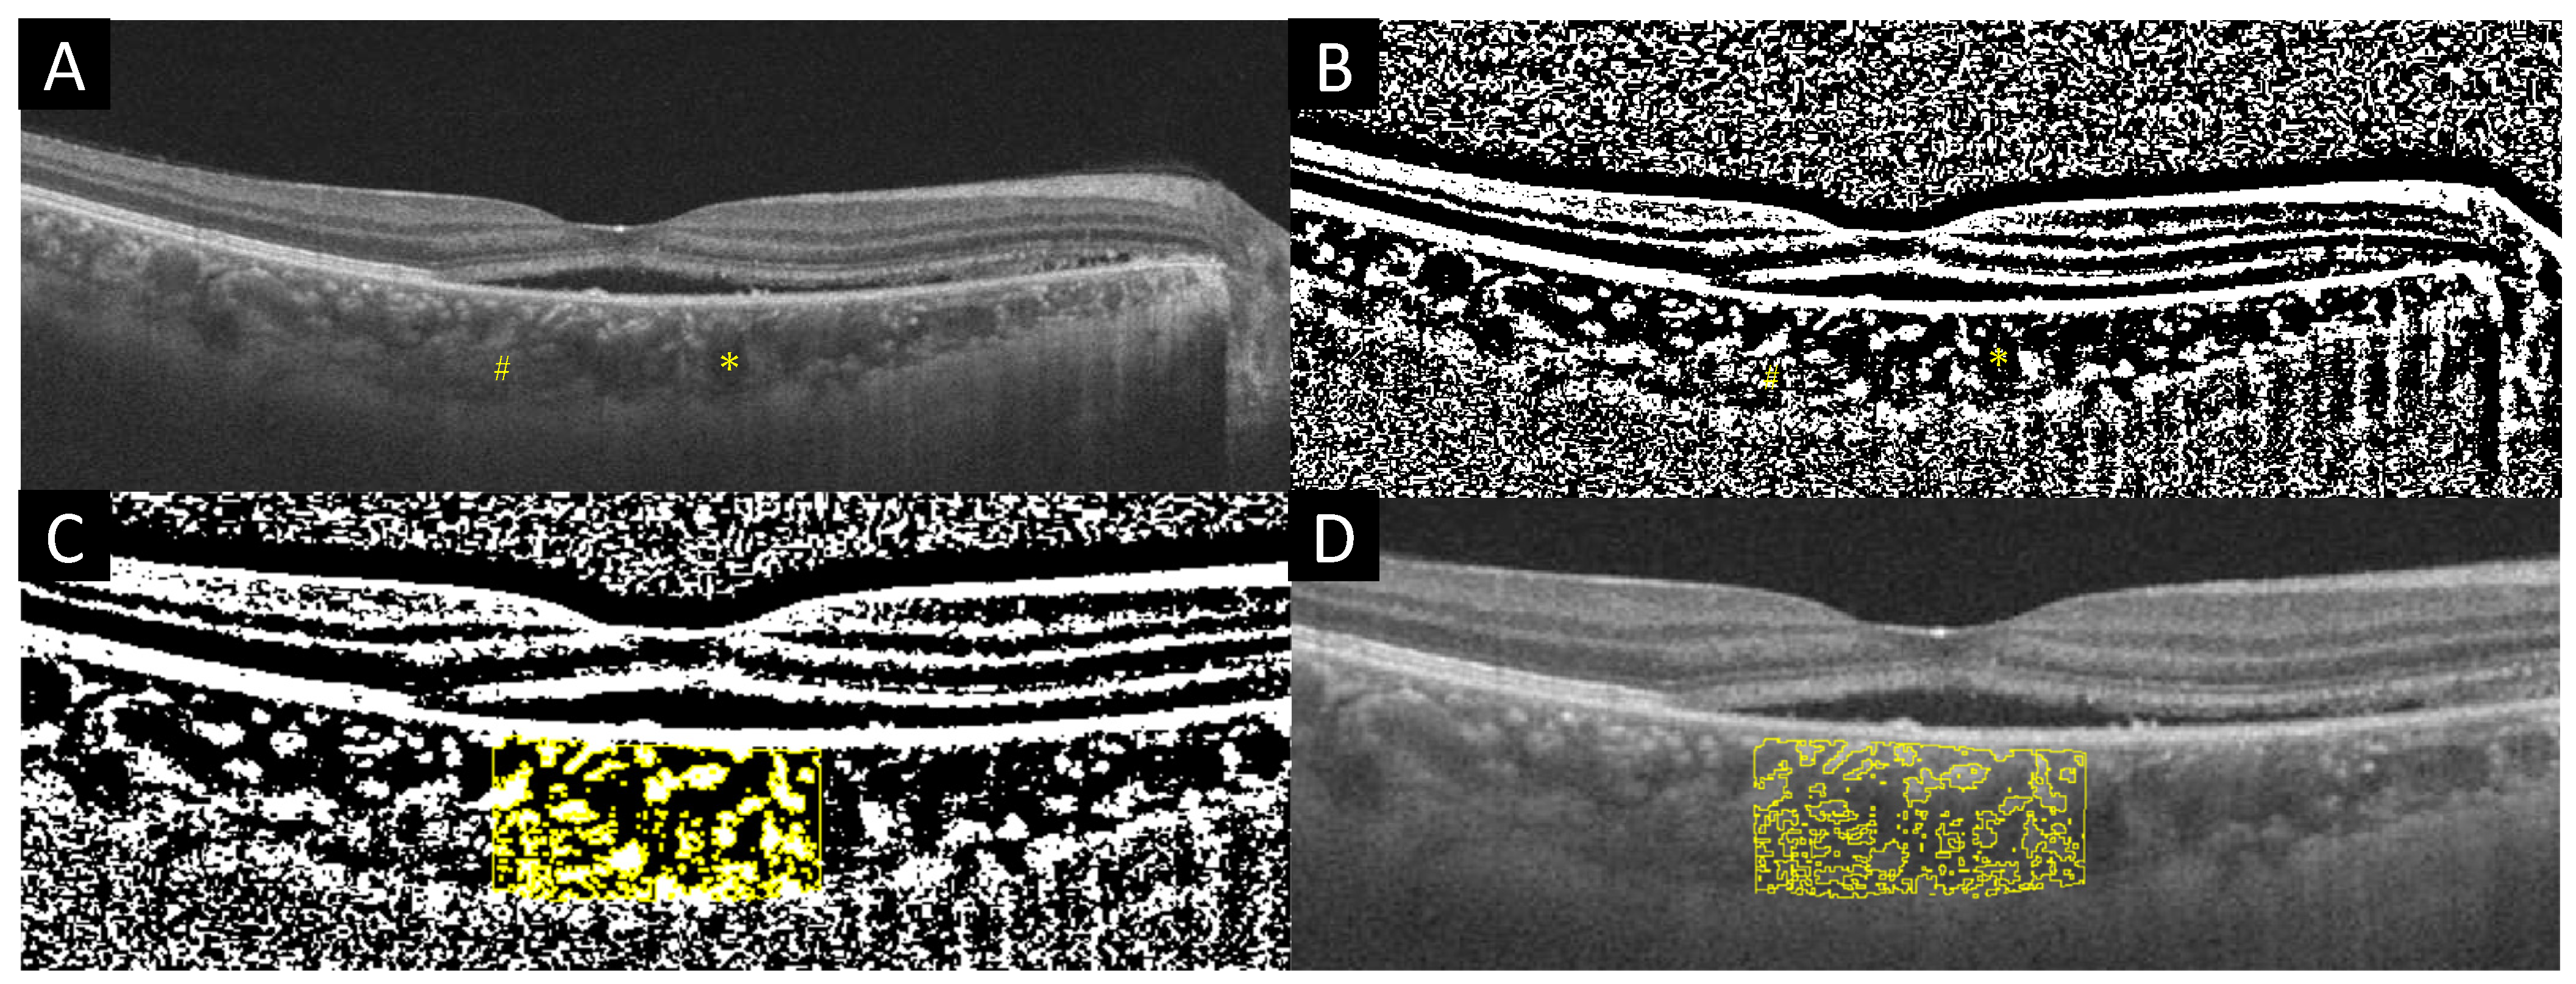

2.2. Measurements